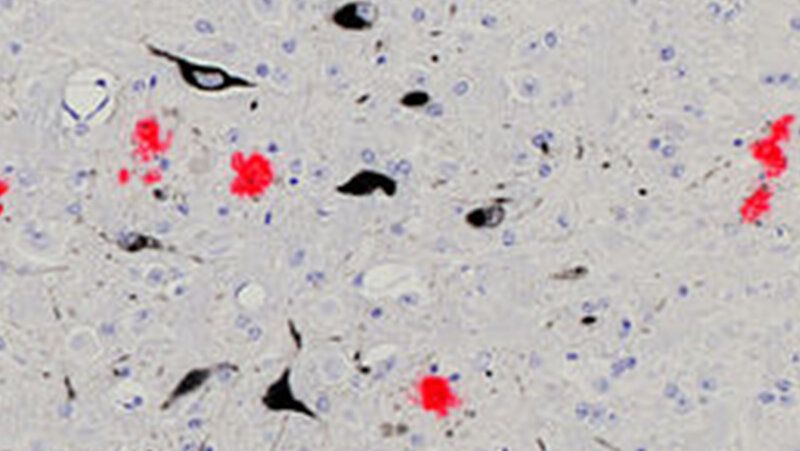

Hauptursache für die Entstehung der Alzheimerkrankheit scheint die Ablagerung eines bestimmen Eiweißes, des Beta-Amyloid-Proteins, im Gehirn zu sein – so der aktuelle Stand der Alzheimerforschung. Die Bildung dieser sogenannten Plaques beginnt mindestens zwanzig Jahre vor den ersten Krankheitssymptomen. Bislang fand man bei Erkrankten jedoch nur einen schwachen Zusammenhang zwischen der Menge der Ablagerungen und den klinischen Symptomen. Grund dafür könnte sein, dass sich die Krankheit in fortschreitenden Stadien unabhängig von den Plaques weiterentwickelt. Das legt eine aktuelle Studie von Forschenden um Prof. Dr. Mathias Jucker vom Hertie-Institut für klinische Hirnforschung, der Universität Tübingen und dem Deutschen Zentrum für Neurodegenerative Erkrankungen (DZNE) nahe. Eine Therapie müsse daher so frühzeitig wie möglich begonnen werden, so Jucker. Die Ergebnisse sind in der aktuellen Ausgabe der renommierten Zeitschrift „Nature Communications“ erschienen.

Das Tübinger Forschungsteam liefert nun erstmals experimentelle Belege für die Entkopplung der Ablagerungen von der nachgeschalteten Neurodegeneration. In ihrer Studie untersuchte es Mäuse, die als Alzheimermodell dienen. Bei ihnen lagern sich – wie bei Alzheimererkrankten – mit fortschreitendem Lebensalter Beta-Amyloid-Eiweiße im Gehirn ab. Die Wissenschaftlerinnen und Wissenschaftler reduzierten nun bei den Mäusen in unterschiedlichen Altersstadien gezielt die Plaques. Dann maßen sie ein weiteres Protein im Hirnwasser der Mäuse, das sogenannte Neurofilament-Leichtketten-Protein (NfL). Das NfL-Protein ist im Hirnwasser von Alzheimererkrankten erhöht; es gilt als Anzeiger für den Abbau von Nervenzellen. Das Ergebnis: „Wenn wir die Beta-Amyloid-Ablagerung in frühen Stadien reduzierten, stieg die Menge an NfL-Protein im Hirnwasser nicht mehr an. Wir konnten den Abbau der Nervenzellen stoppen“, so Christine Rother, Erstautorin der Studie. Ein anderes Bild ergab sich im höheren Lebensalter: „Wenn wir die Bildung der Beta-Amyloid-Plaques in späteren Stadien reduzierten, stieg der Pegel des NfL-Proteins im Hirnwasser unverändert an. Es starben also weiterhin Nervenzellen. Die Neurodegeneration hatte sich von den Ablagerungen entkoppelt“, ergänzt Ruth Uhlmann, Co-Erstautorin der Arbeit. „Es scheint bei Alzheimer also zwei Phasen der Krankheitsentwicklung zu geben“, schlussfolgert Jucker. In der ersten Phase trieben die Beta-Amyloid-Plaques die Krankheit voran. Zu diesem Zeitpunkt seien Therapien, die den Ablagerungen entgegenwirken, höchst effektiv. In der zweiten Phase schreite hingegen die Neurodegeneration unabhängig von den Plaques fort. Gegen die Beta-Amyloid-Plaques gerichtete Therapien verfehlen nun weitgehend ihre Wirkung.